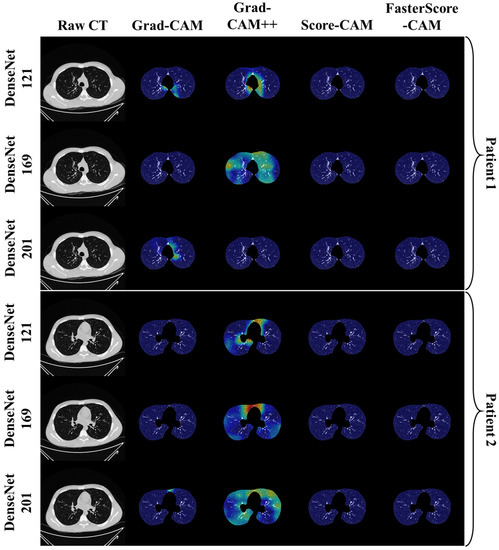

Visual Results Representing Lesion Using the Four CAM Techniques